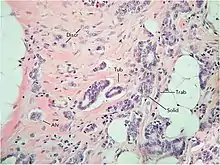

Krakhmal et al. have studied the features of breast cancer progression depending on intratumoral heterogeneity. Attention has been paid to the phenotypic diversity of the primary tumor in invasive carcinoma of no special type, which accounts for the bulk (80%) of all histological types of breast cancer.[2]

Despite the structural diversity of the primary breast tumor, five main types of morphological structures can be distinguished: alveolar, trabecular, tubular and solid structures, and discrete groups of tumor cells. The alveolar structures are tumor cell clusters of round or slightly irregular shape. The morphology of the cells that form this type of structures varies from small cells with moderate cytoplasm and round nuclei to large cells with hyperchromatic nuclei of irregular shape and moderate cytoplasm. The trabecular structures are either short, linear associations formed by a single row of small, rather monomorphic cells or wide cell clusters consisting of two rows of medium-sized cells with moderate cytoplasm and round normochromic or hyperchromatic nuclei. The tubular structures are formed by a single or two rows of rather monomorphic cells with round normochromic nuclei. The solid structures are fields of various sizes and shapes, consisting of either small cells with moderate cytoplasm and monomorphic nuclei or large cells with abundant cytoplasm and polymorphic nuclei. Discrete groups of cells occur in the form of clusters of one to four cells with variable morphologies.[2]

The different morphological structures of breast tumors correspond to certain types of invasion. Therefore, alveolar, trabecular, and solid structures that are characterized by the presence of cell-cell contacts may be referred to morphological manifestations of collective migration, while discrete groups of tumor cells may be referred to manifestations of individual migration. The first batch of data obtained in a study of the expression of cell adhesion genes confirms this hypothesis. For example, there was a decrease in the activity of the genes of cadherins, which are responsible for cell-cell contacts, in the order: solid – alveolar and trabecular structures – discrete groups of tumor cells. In this case, the number of expressed genes of integrins involved in the adhesion of tumor cells to the extracellular matrix was reduced in the order: solid and alveolar – trabecular structures – discrete groups of tumor cells.[2]